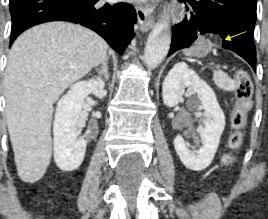

Riñones poliquísticos

Elevación bilateral por riñones poliquísticos. Hernia hiatal ¡Sin gas en abdomen!